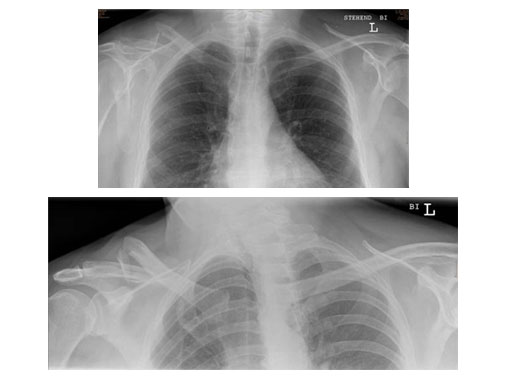

Case 1: Male, 56 years, Bicycle accident